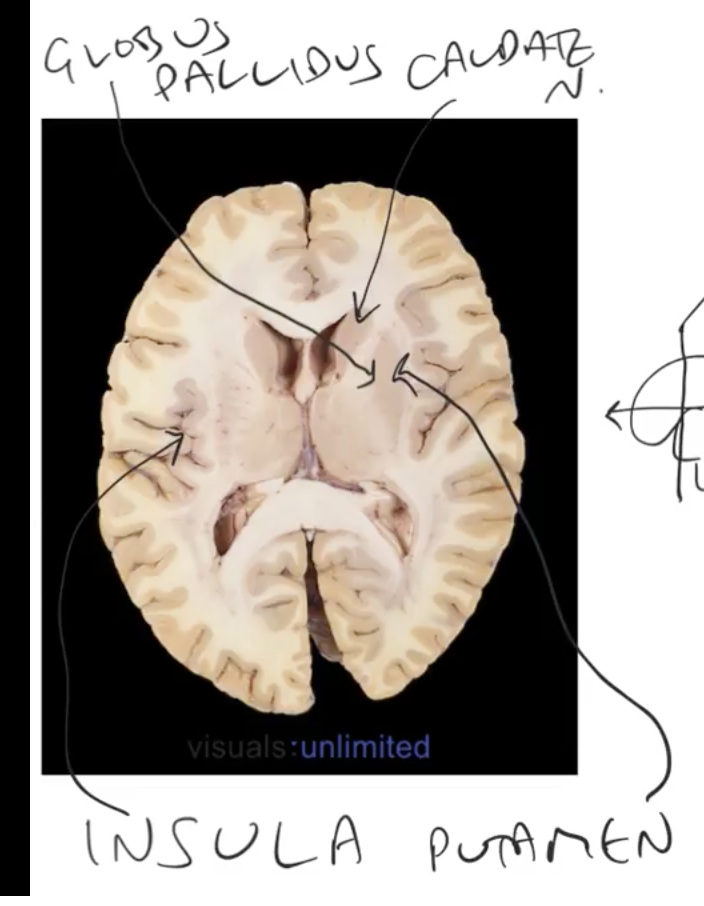

label

Caudate> C-shaped structure

appears twice

what r the white mater strucutres?

corpus callosum & v-shaped internal capsule

where does corpus callosum run?

above the lateral ventricles

what is this? fucntion? location

internal capsule

connects cerebral cortex w/ the rest of the nervous system

its a major white matter pathway!

its sandwhiched w=btw 2 majir grey matters!